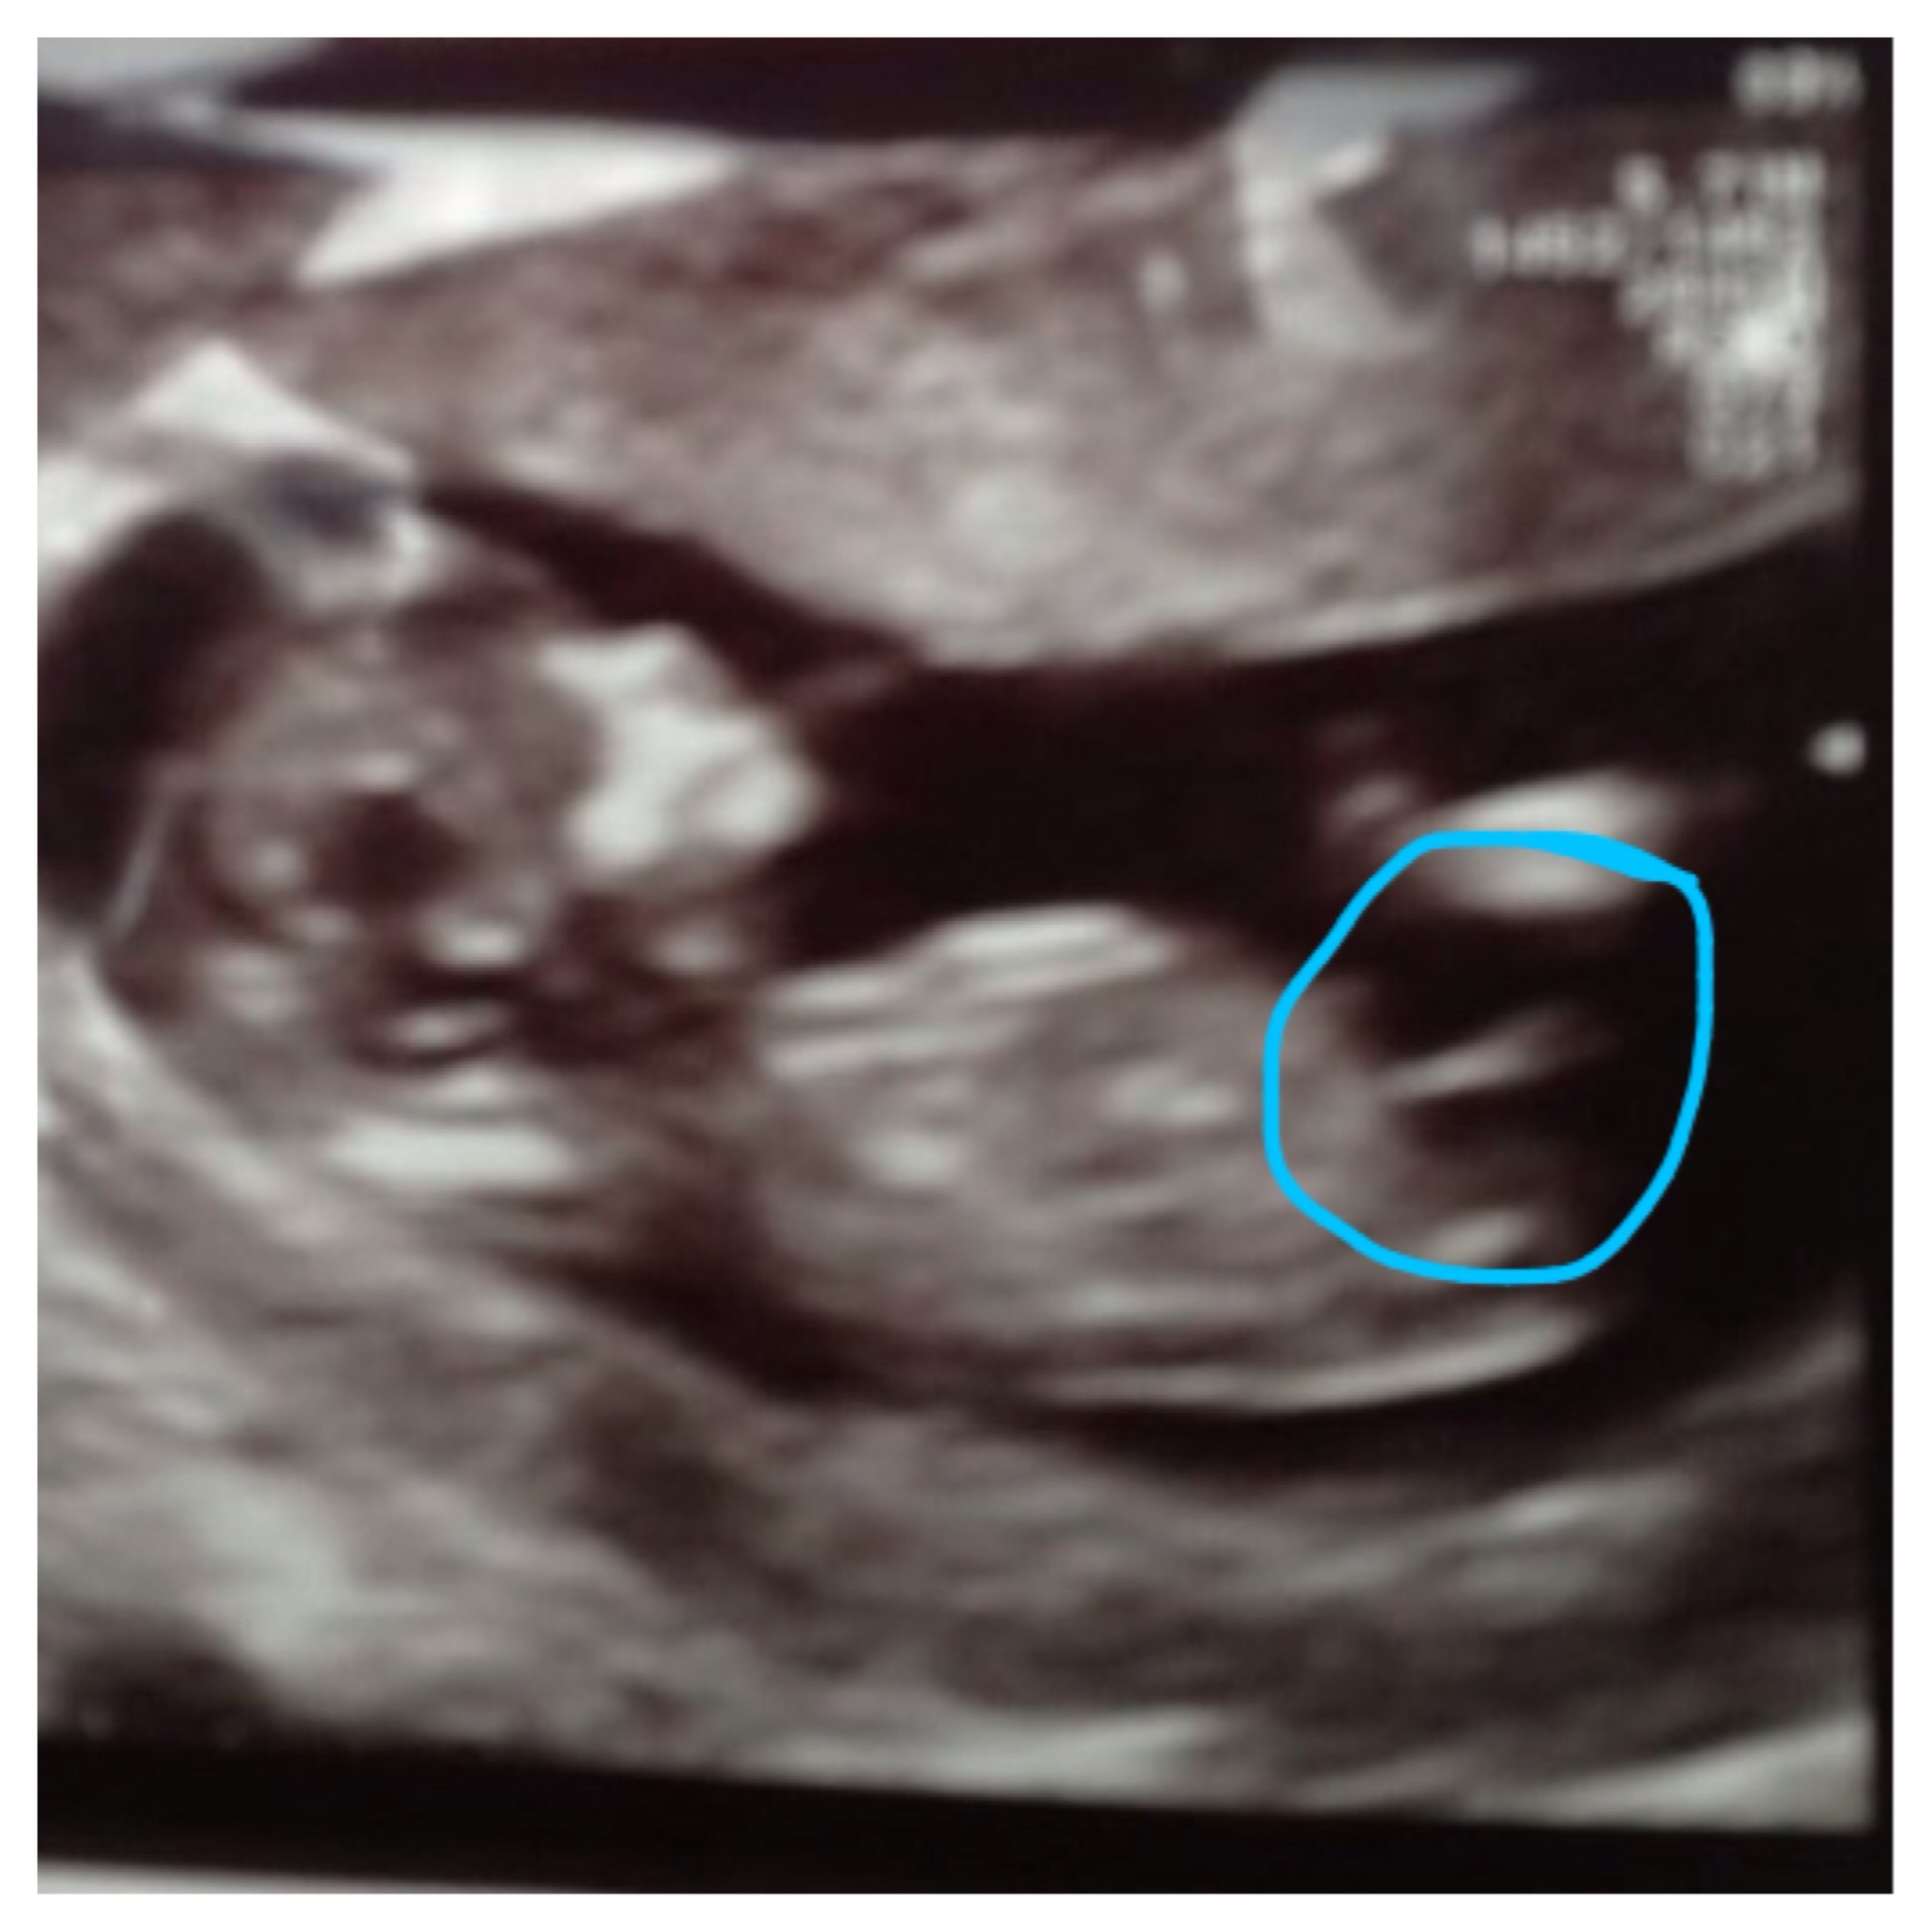

I was told boy by 20 people and now 2 people told me this is

Not the nub..

Any guesses?

Almost 100% that's the nub in the first pic and a boy nub.

Looks like the nub to me, and yep, that's a boy nub!

I'd say that's the nub! Id also say kinda girl... Looks parallel to the spine, I'm no expert tho.

Definitely the nub!

That is definitely the nub and Im leaning slightly more Blue!

Good luck at your scan. I also think it looks like a boy nub

Ya know, I'm not sure on this one. It's kind of in that grey area that could go either way.